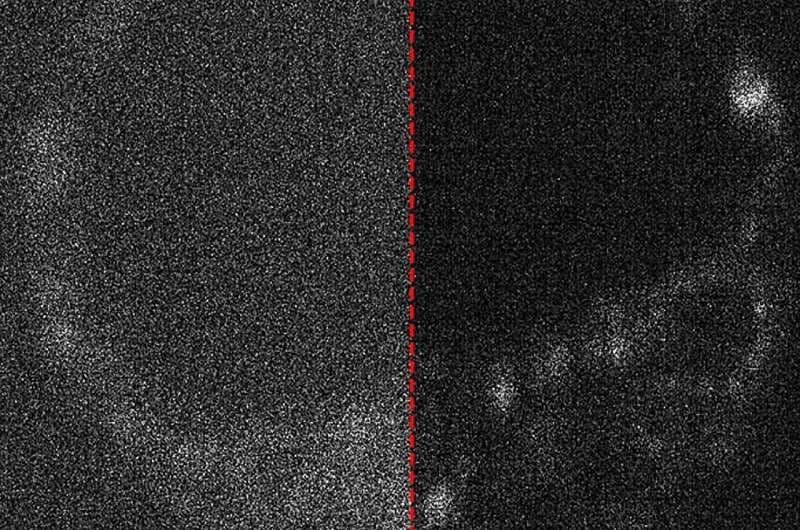

Анализ изображений стал возможен благодаря сочетанию экспертизы в области оптики, биологии, лазерной физики и микроскопии. Исследователи также изучили возможности использования искусственного интеллекта для удаления шумов с полученных изображений, которые возникают из-за недостаточного количества света при съёмке.